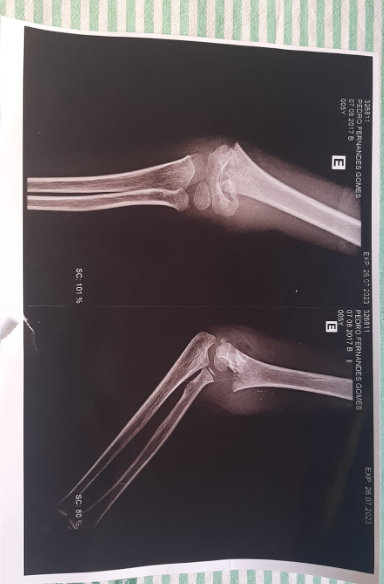

Desespero - De acordo com Everton, sua esposa ligou para ele desesperada. "Quando cheguei na escola, meu filho gritava de dor, peguei ele e fui correndo pro hospital, após exames foi constado que ele tinha quebrado o braço esquerdo e que precisava passar por cirurgia de emergência. Meu filho foi internado na Santa Casa e passou por cirurgia e colocação de 2 fios pra sustentação da parte que foi lesionada", relatou Everton ao Visão Notícias.

Naquela unidade médica, foi constatado que o braço direito do garotinho tinha fraturado e foi imobilizado. A família informou a escola e, segundo disseram, nenhuma providência foi tomada.